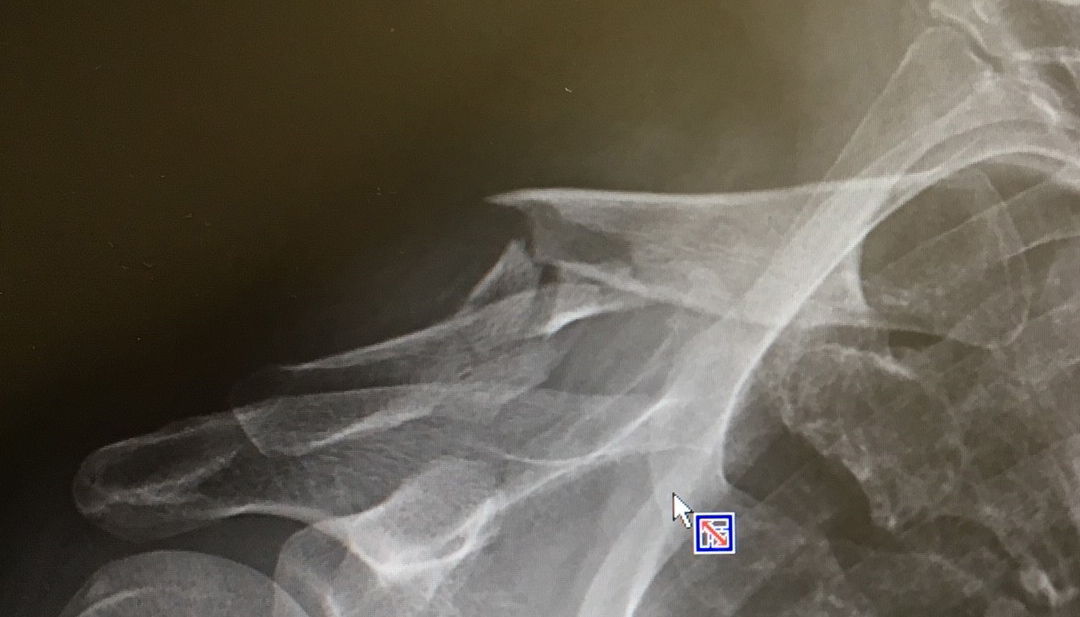

そして右肩に手をやると、鎖骨の一部が極端に飛び出しているのに触れました。

あーあ。一瞬でわかりました。一応、医者なので。

「大丈夫、いや大丈夫ではないが。鎖骨が折れた」

翌日、優秀な整形外科医の友人を受診、立派に折れた鎖骨のレントゲン写真を見せてもらいました。

そんなわけで、10/29入院でプレート固定の手術をします。